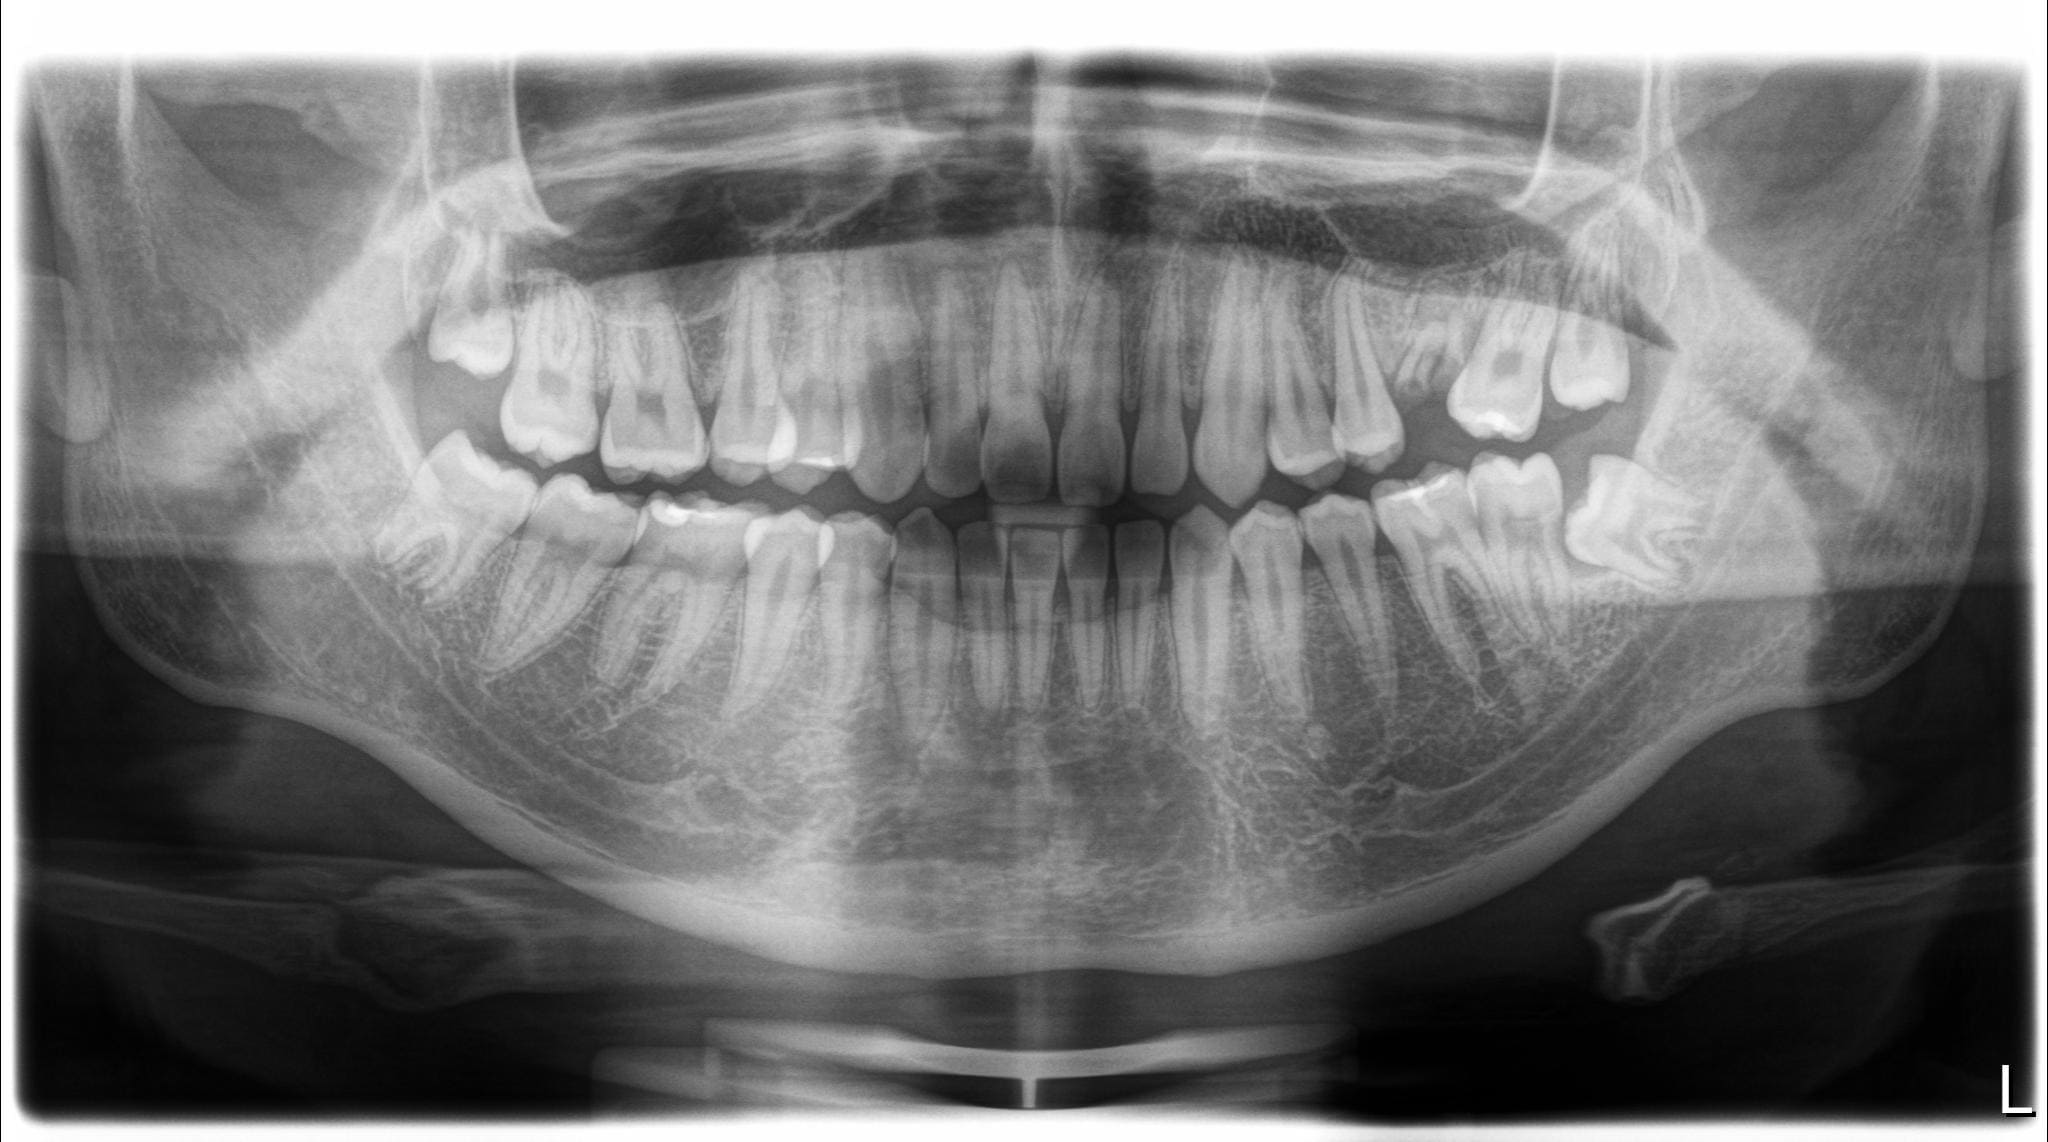

病患在三年前第一次來到森釉診所,當時的主訴是因為覺得自己的牙齒排列不夠整齊,特別是後方缺牙的地方,旁邊的牙齒已經開始往缺牙處倒塌,加上下巴有些往前突出的情況,希望我們能夠幫他進行完整的矯正評估和治療規劃。

經過仔細檢查後,我們發現病患的口腔狀況存在幾個需要處理的問題。首先是左上方的臼齒因為嚴重蛀牙只剩下牙根,導致兩側的牙齒失去支撐而逐漸傾倒,進而影響了整體的牙齒排列。另外,下排牙齒有錯咬的狀況,造成下巴看起來往前凸。除此之外,由於病患本身的牙齒比例偏短,笑的時候牙齦露出的面積相對比較多,影響了整體的美觀性。